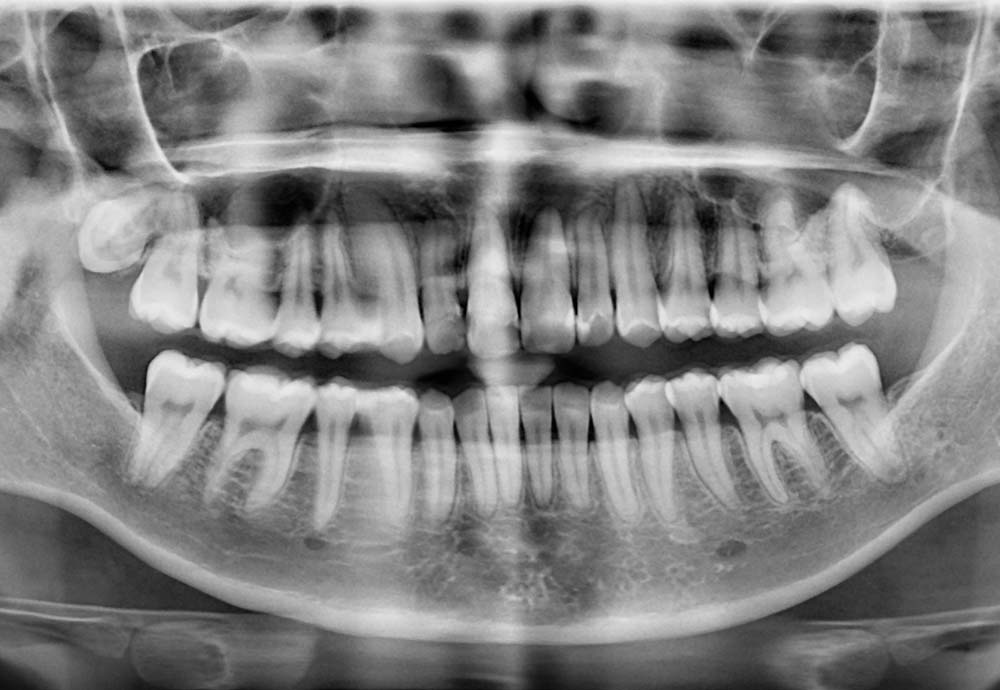

Wisdom teeth may need to be removed if they are impacted, causing pain, swelling, infection, or damage to nearby teeth.

Other reasons include preventing future dental problems such as decay, gum disease, cysts, or crowding of your existing teeth.

Removing all wisdom teeth at once is usually not recommended, as it may require general anesthesia and could increase certain risks.